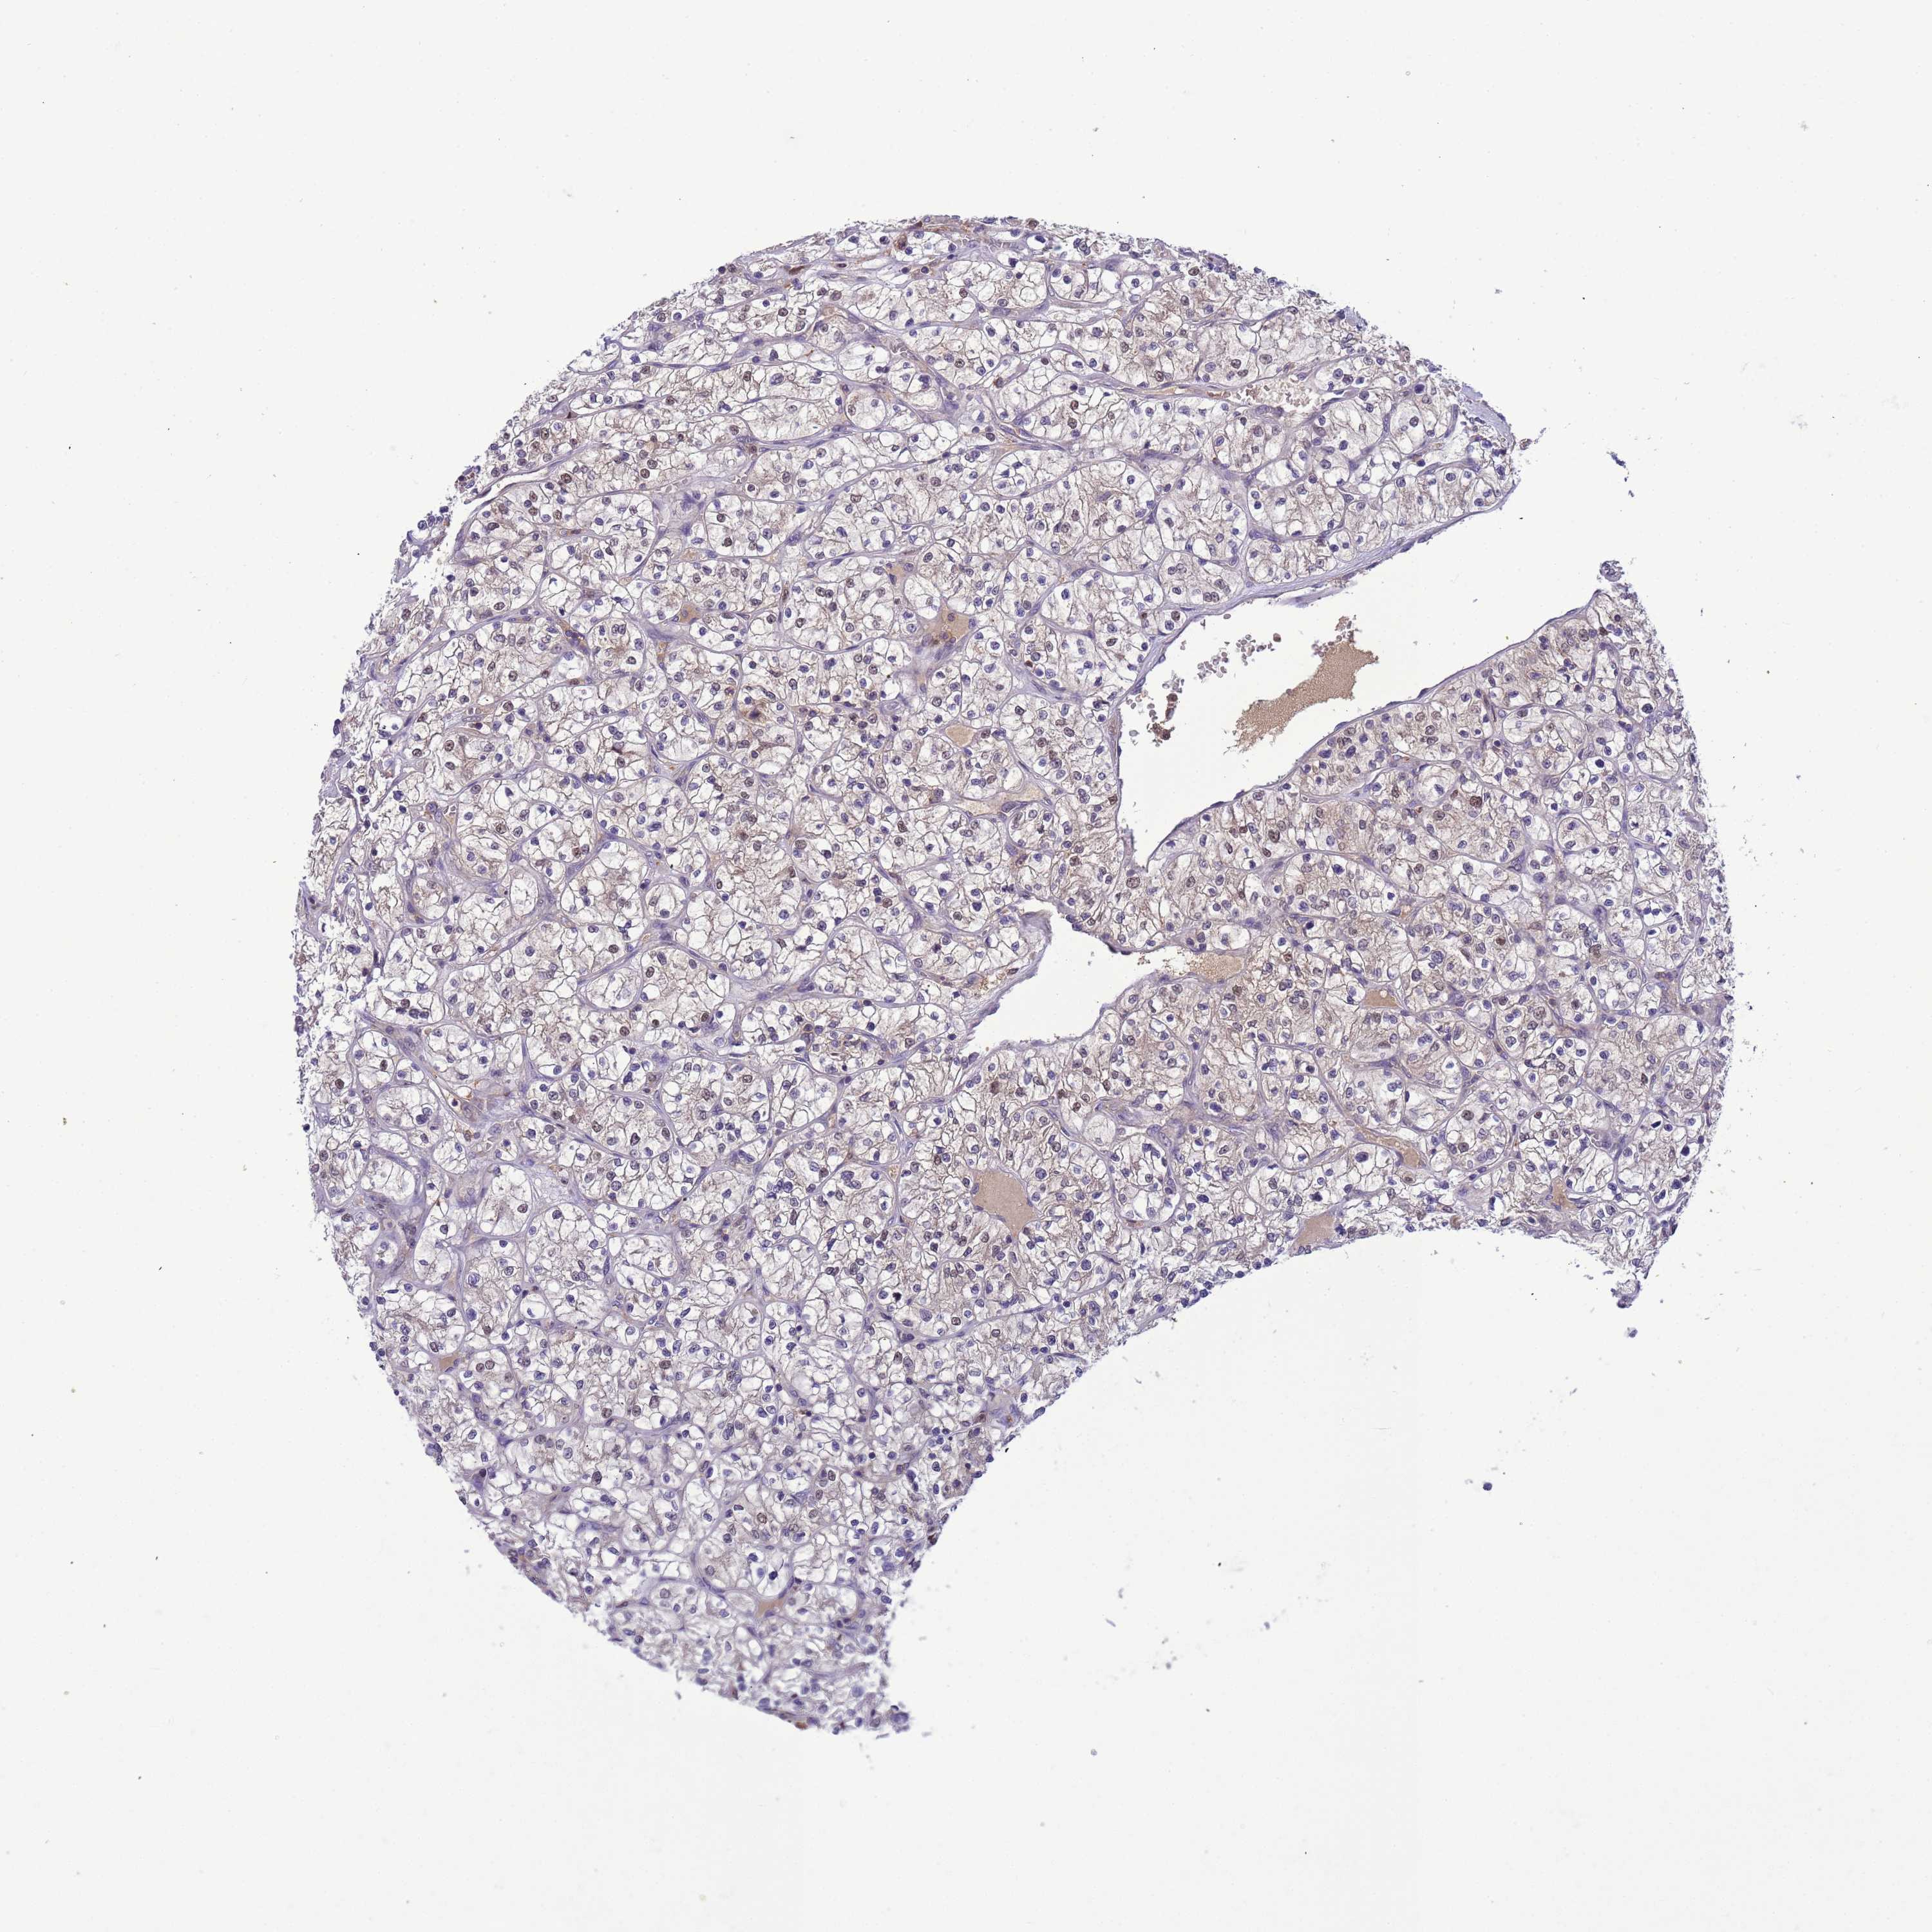

KIDNEY RENAL CLEAR CELL CARCINOMA (VALIDATION) - Interactive survival scatter ploti

The Survival Scatter plot shows the clinical status (i.e. dead or alive) for all individuals in the patient cohort, based on the same data that underlies the corresponding Kaplan-Meier plots. Patients that are alive at last time for follow-up are shown in blue and patients who have died during the study are shown in red.

& Survival analysisi

Kaplan-Meier plots summarize results from analysis of correlation between mRNA expression level and patient survival. Patients were divided based on level of expression into one of the two groups "low" (under cut off) or "high" (over cut off). X-axis shows time for survival (years) and y-axis shows the probability of survival, where 1.0 corresponds to 100 percent.

CD53 is not prognostic in Kidney Renal Clear Cell Carcinoma (validation)

Best expression cut offi

: 96.59

Average pTPM 93.5

Number of samples 100